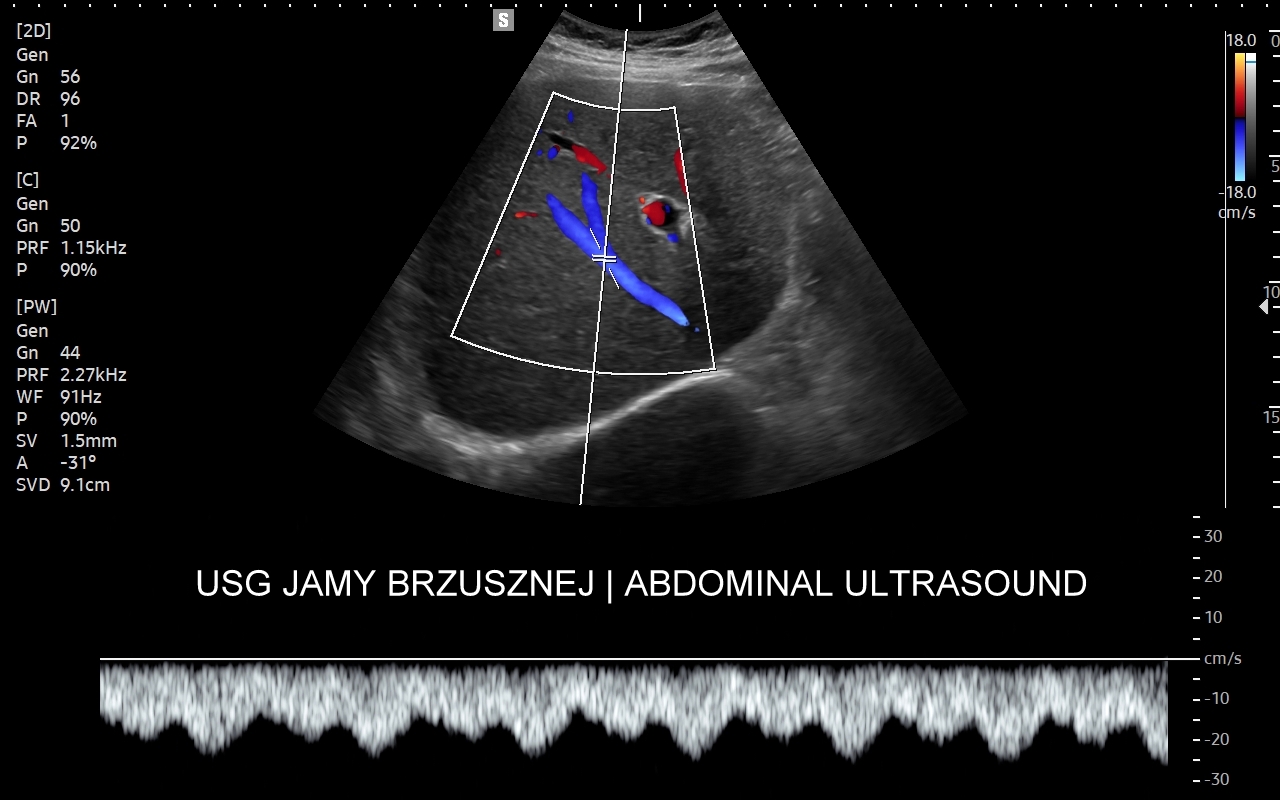

Badanie multiparametryczne MPUS jamy brzusznej

Rozwinięciem standardowego badania USG jamy brzusznej jest badanie multiparametryczne MPUS (ang. multiparametric ultrasound), w ramach którego wykorzystuje się różnorodne, nowoczesne modalności sonograficzne, takie jak tryby mikrounaczynienia MVI, B-flow, elastografię, ilościową ocenę stłuszczenia wątroby QUS, czy tryb Dopplera spektralnego, a to wszystko w celu uzyskania dodatkowej oceny funkcjonalnej i biologicznej struktur, narządów oraz tkanek jamy brzusznej. Obrazowanie MPUS niejednokrotnie poprawia także wizualną ocenę narządów wewnętrznych, czego przykładem jest zastosowanie trybu MVI w ramach bezkontrastowej angiografii sonograficznej naczyń oraz w ocenie guzów nerek. Klasycznymi i najczęstszymi zastosowaniami badania MPUS są jednakże funkcjonalna ocena wątroby w kierunku stłuszczenia, zwłóknienia, zapalenia i nadciśnienia wrotnego, a także ocena żywotności i funkcji nerek.